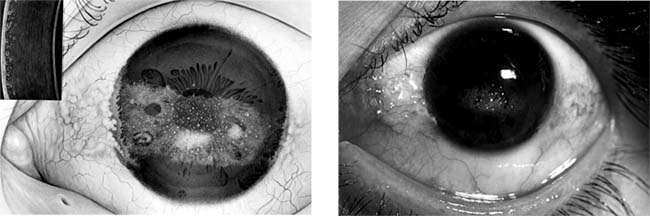

Figure 6-11

Figure 6-11: Keratoconus.

Figure 6-13

Figure 6-13: Two photos showing climatic droplet (Labrador) keratodystrophy. Inset at left shows slitlamp view. (Photo at left courtesy of A Ahmad.)